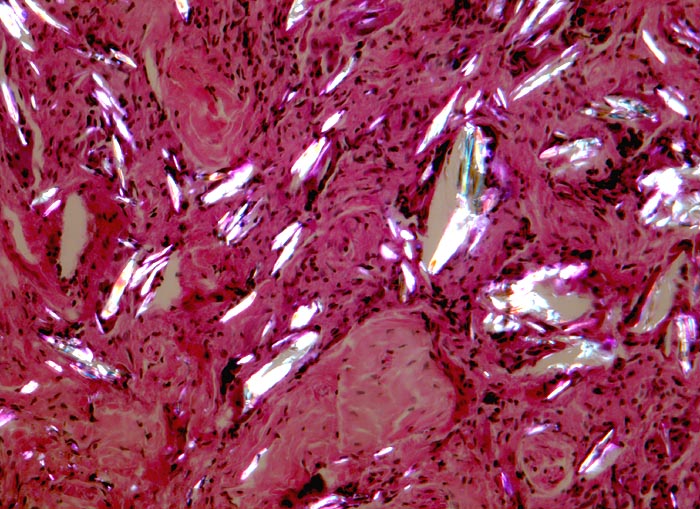

PathoPic ID 4658 - Fremdkörpergranulom

Fremdkörpergranulom

Artefakt / Fremdkörper / Pigment

Weichteile

Doppelbrechung: Entzündlich infiltriertes Bindegewebe mit hell aufleuchtendem doppelbrechendem, kristalloidem Fremdmaterial, welches teilweise von

Fremdkörperriesenzellen umgeben oder von Ihnen eingeschlossen ist.

Histologie

160